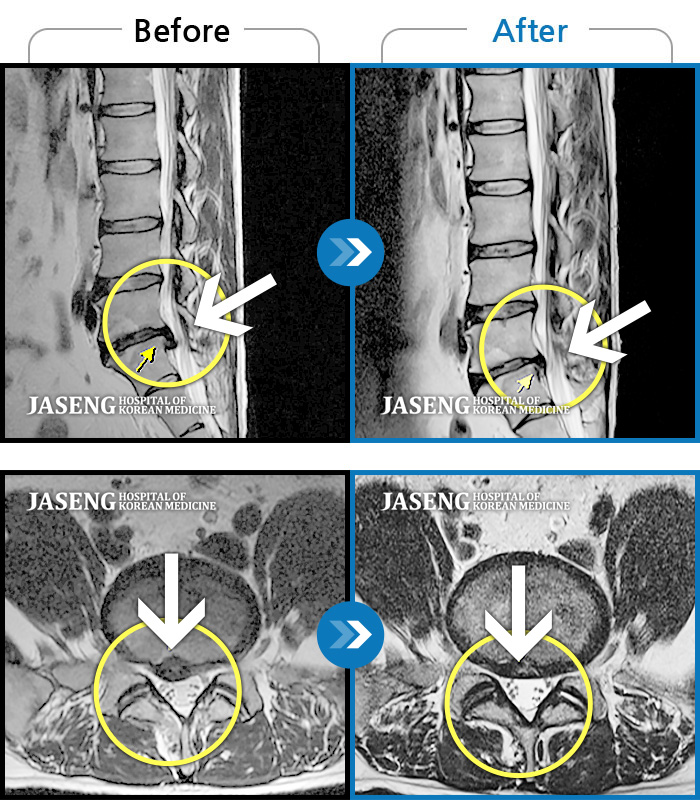

허리디스크

광주 · 장영우 원장

양측 허리부터 골반 묵직한 통증, 좌측 다리 외측까지 이어지는 당기는 통증으로 내원하셨습니다.

촬영시기

2503.04.01 ~ 2509.11.01